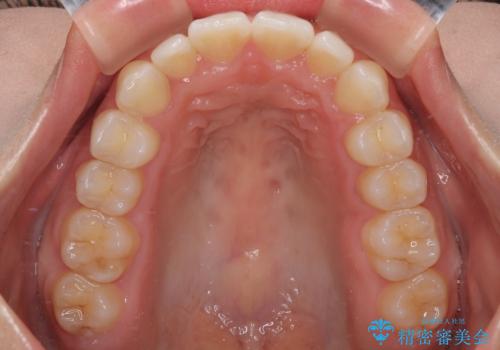

治療終了時

前歯が自然なアーチにきれいに並び、正中(上下の中心線)も整い、咬み合わせも良好です。

側方拡大することで、非抜歯であるにも関わらず前歯が前方に出ることなく、バランスの良い仕上がりとなりました。

「矯正装置が目立たず、思ったより短期間で仕上がりに満足しています。鏡を見るのが毎日楽しみになりました!」とうれしいお言葉をいただきました。